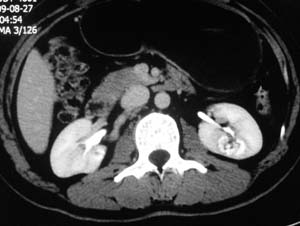

以下是引用子期在2010-3-19 20:47:00的发言:[br]血管畸形的ct增强应该有明显强化,本例并不相符合。本例双肾局部的略低密度影,累及肾盂,局部皮质明显变薄、内陷,增强扫描有轻度的强化,应考虑为炎性病变,患者为年轻男性,累及双肾的感染以结核较常见,可以没有明显的临床症状,尿中有时候也并不能查出什么;肾脓肿常有明显感染中毒症状,本例不符,另外一般的肾盂肾炎或肾小球肾炎通过小便就可确诊,其它还不能排除的是黄色肉芽肿性肾盂肾炎,然而单凭ct一般也很难鉴别。